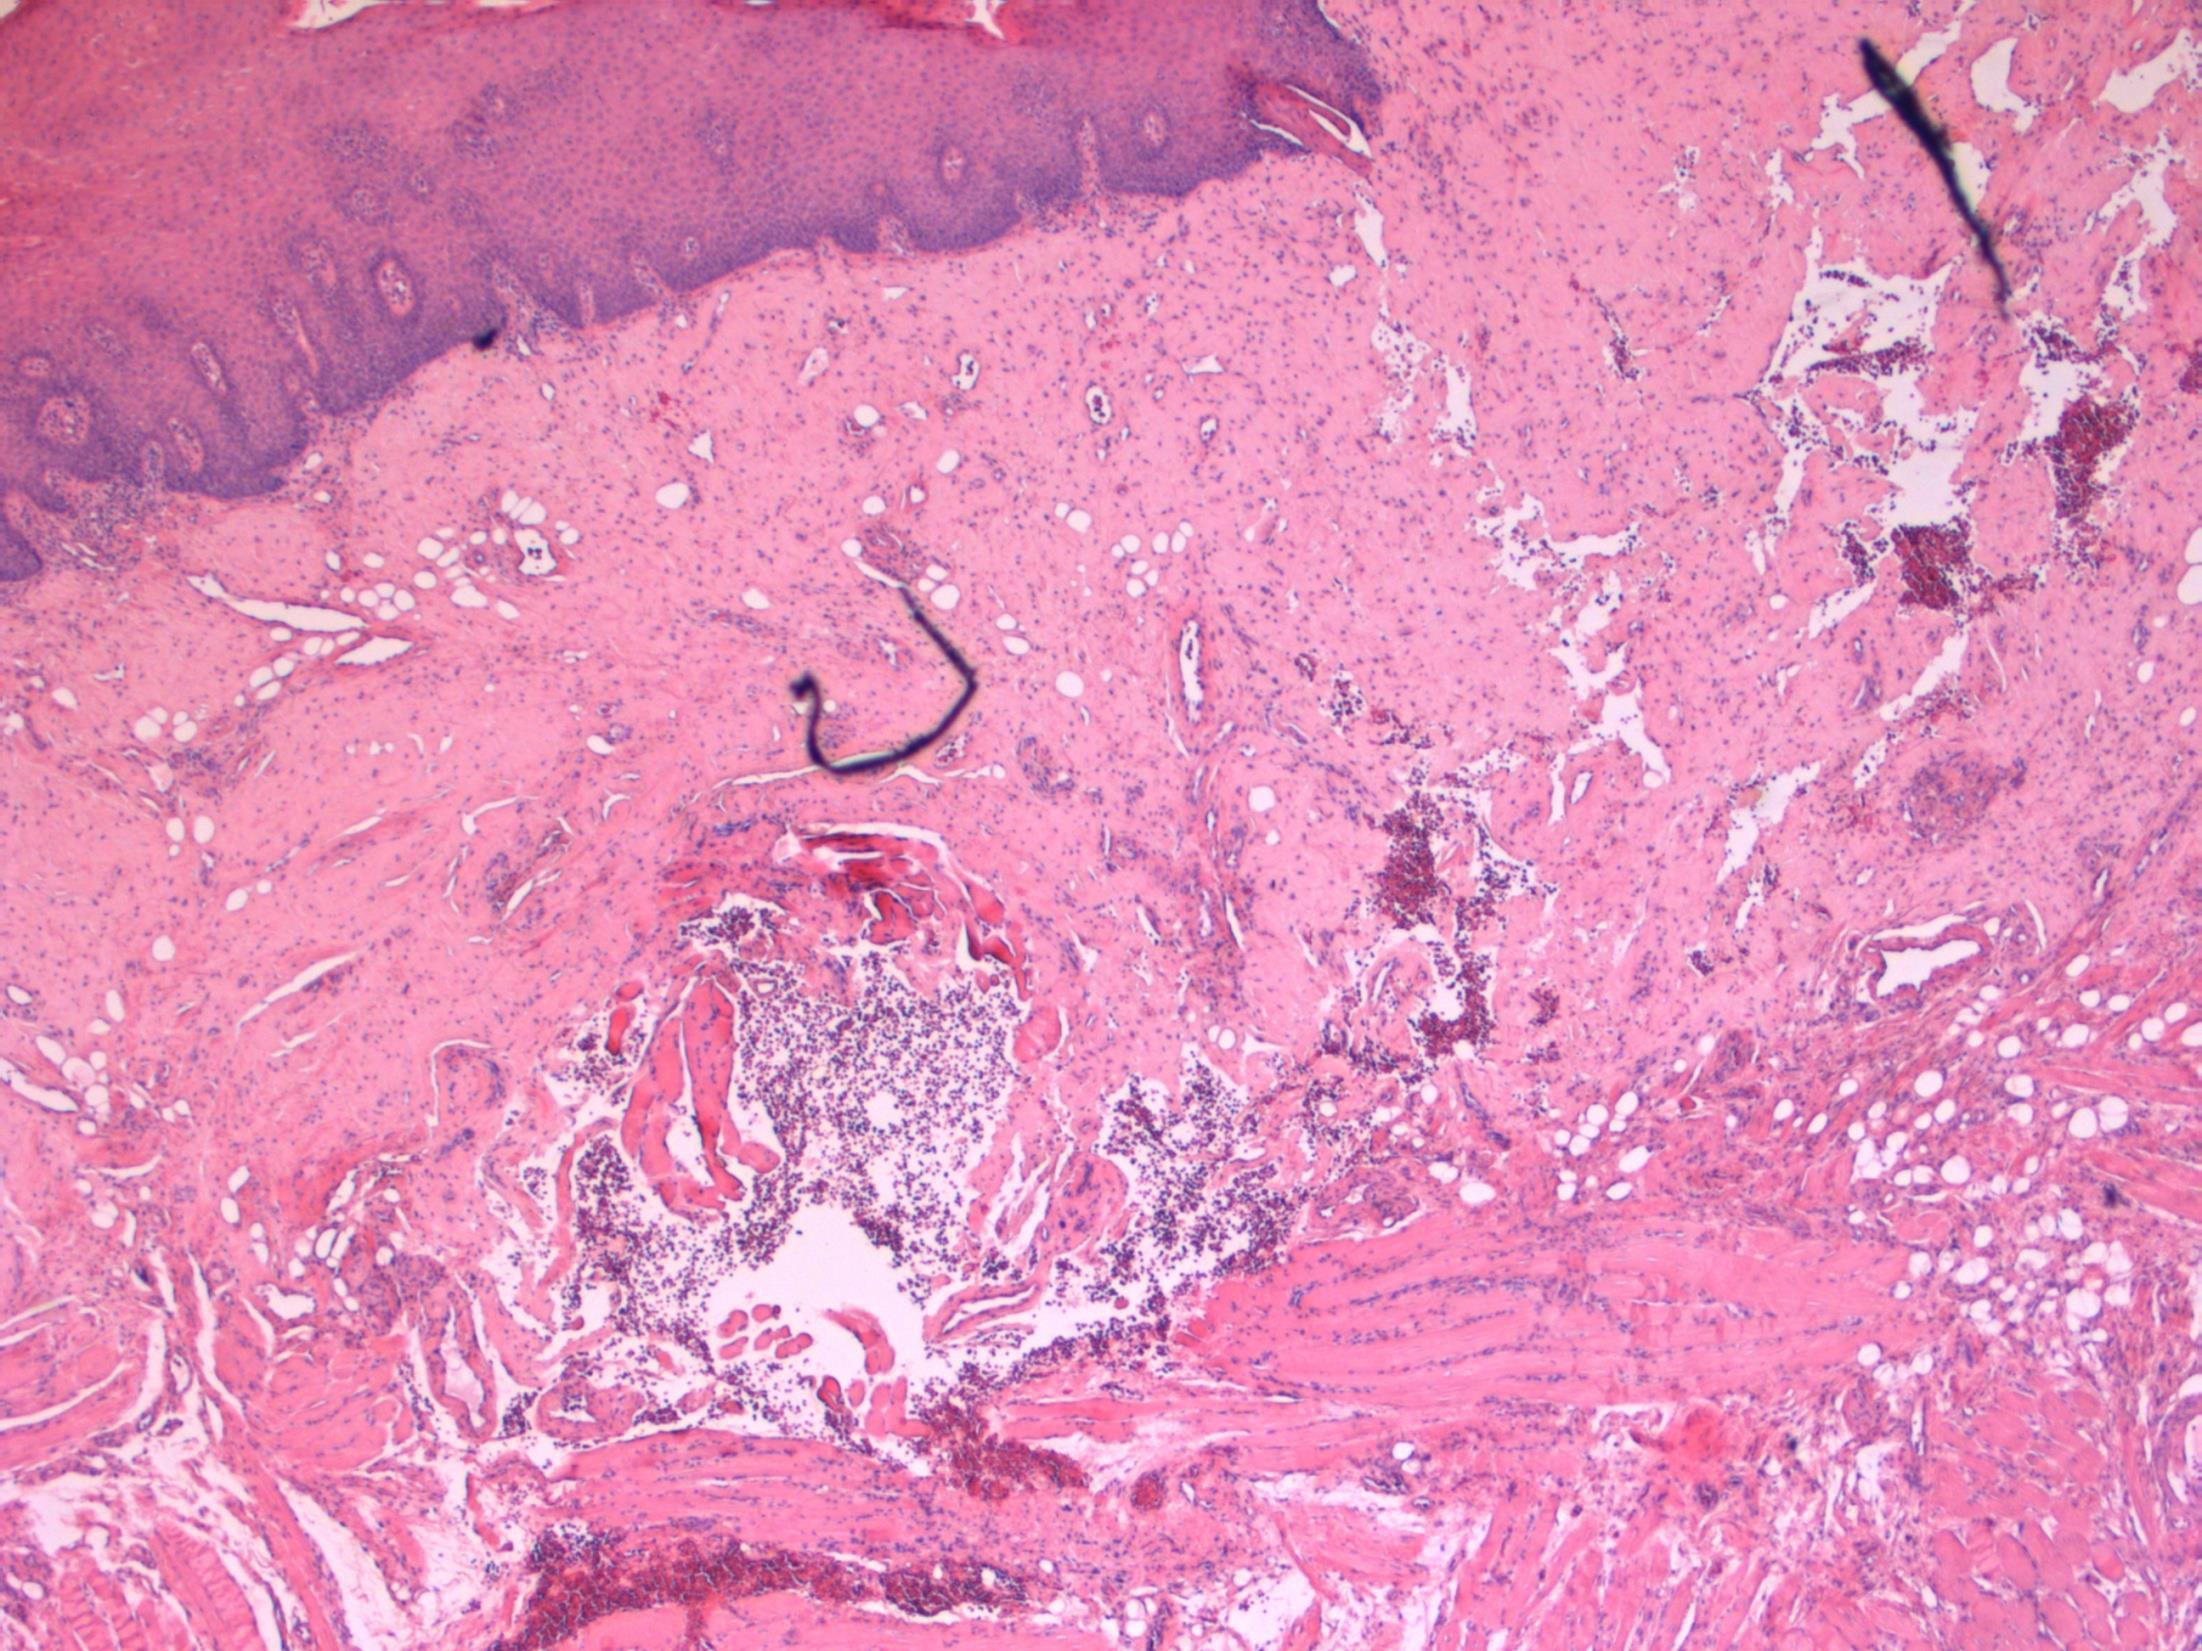

28F Acute abdominal pain. Laparoscopy showed torted large right ovary, ?Ovarian cyst. Excised. Macro- Ovary measuring 9x8x5cm with a solid and soft cut surface. No cyst seen.

• Ovary – Massive ovarian oedema

Massive ovarian oedema

Description: Diffuse oedema of medulla and inner cortex; relative sparing of outer cortex. Associated RBC extravasation, congestion, inflammation. No cyst seen. No evidence of malignancy.

Diagnosis: Massive ovarian oedema

Differential Diagnosis:

• Fibroma/ fibrothecoma. May show marked oedema but tumour usually replaces entire ovary with no sparing at edges.

• Krukenberg tumour. Can look similar macroscopically and malignant cells can be sparse. Usually older females but can occur in younger females.

Plan:

• Extra blocks to exclude sparse tumour cells.

• Correlate with radiology.

Comments:

Partial torsion of an otherwise normal ovary.

Common in 2nd and 3rd decade – like this case.

Macroscopically a featureless myxoid enlarged ovary (correlates with macro features).

3.5 Cause, prognosis, treatment etc 3.0 Differential diagnostic considerations 2.5 Description with diagnosis 2.0 Other benign diagnosis with no consideration of ovarian oedema 1.5 Differential diagnosis, favouring malignant 1.0 Definite malignant diagnosis Case 7